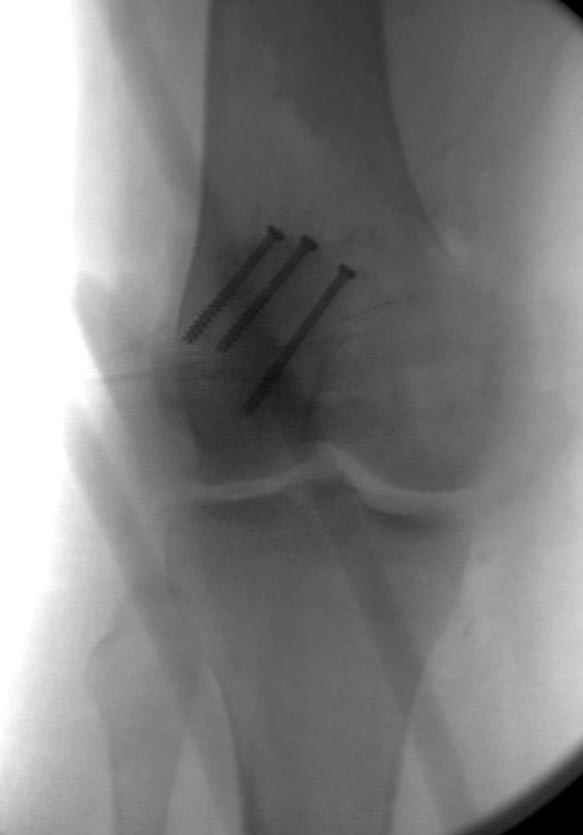

Сегодня досылаю остальные снимки, которые не прошли вчера. Как вчера писал, после фиксации перелома надколенника с дефектом кости и собственной связки, наложили ваккуум и наружный фиксатор. (снимки 4-9)

Внешний фиксатор держим около 6 недель, поэтому был выбран метод фиксации шурупами и еще линия перелома была диагональной, не было нужды в tension band technique, cannulated screws удобнее, провел спицы и по ним шурупы.

Связка ушита обычными сухожильными швами конец в конец, не было нужды проведения шва через надколенник, из-за ех-фиксатора.

На слайдах (не четко обозначены бедро и голень): на бедре по наружно-передней поверхности, между вастус латералис и прямой головками, а на голени по передне-медиальной поверхности, желателен подбор длины резьбовой части стержня по ширине поперечника кости. На снимке: дистальное кольцо, метод проведения стержня через канюлю-проводник.